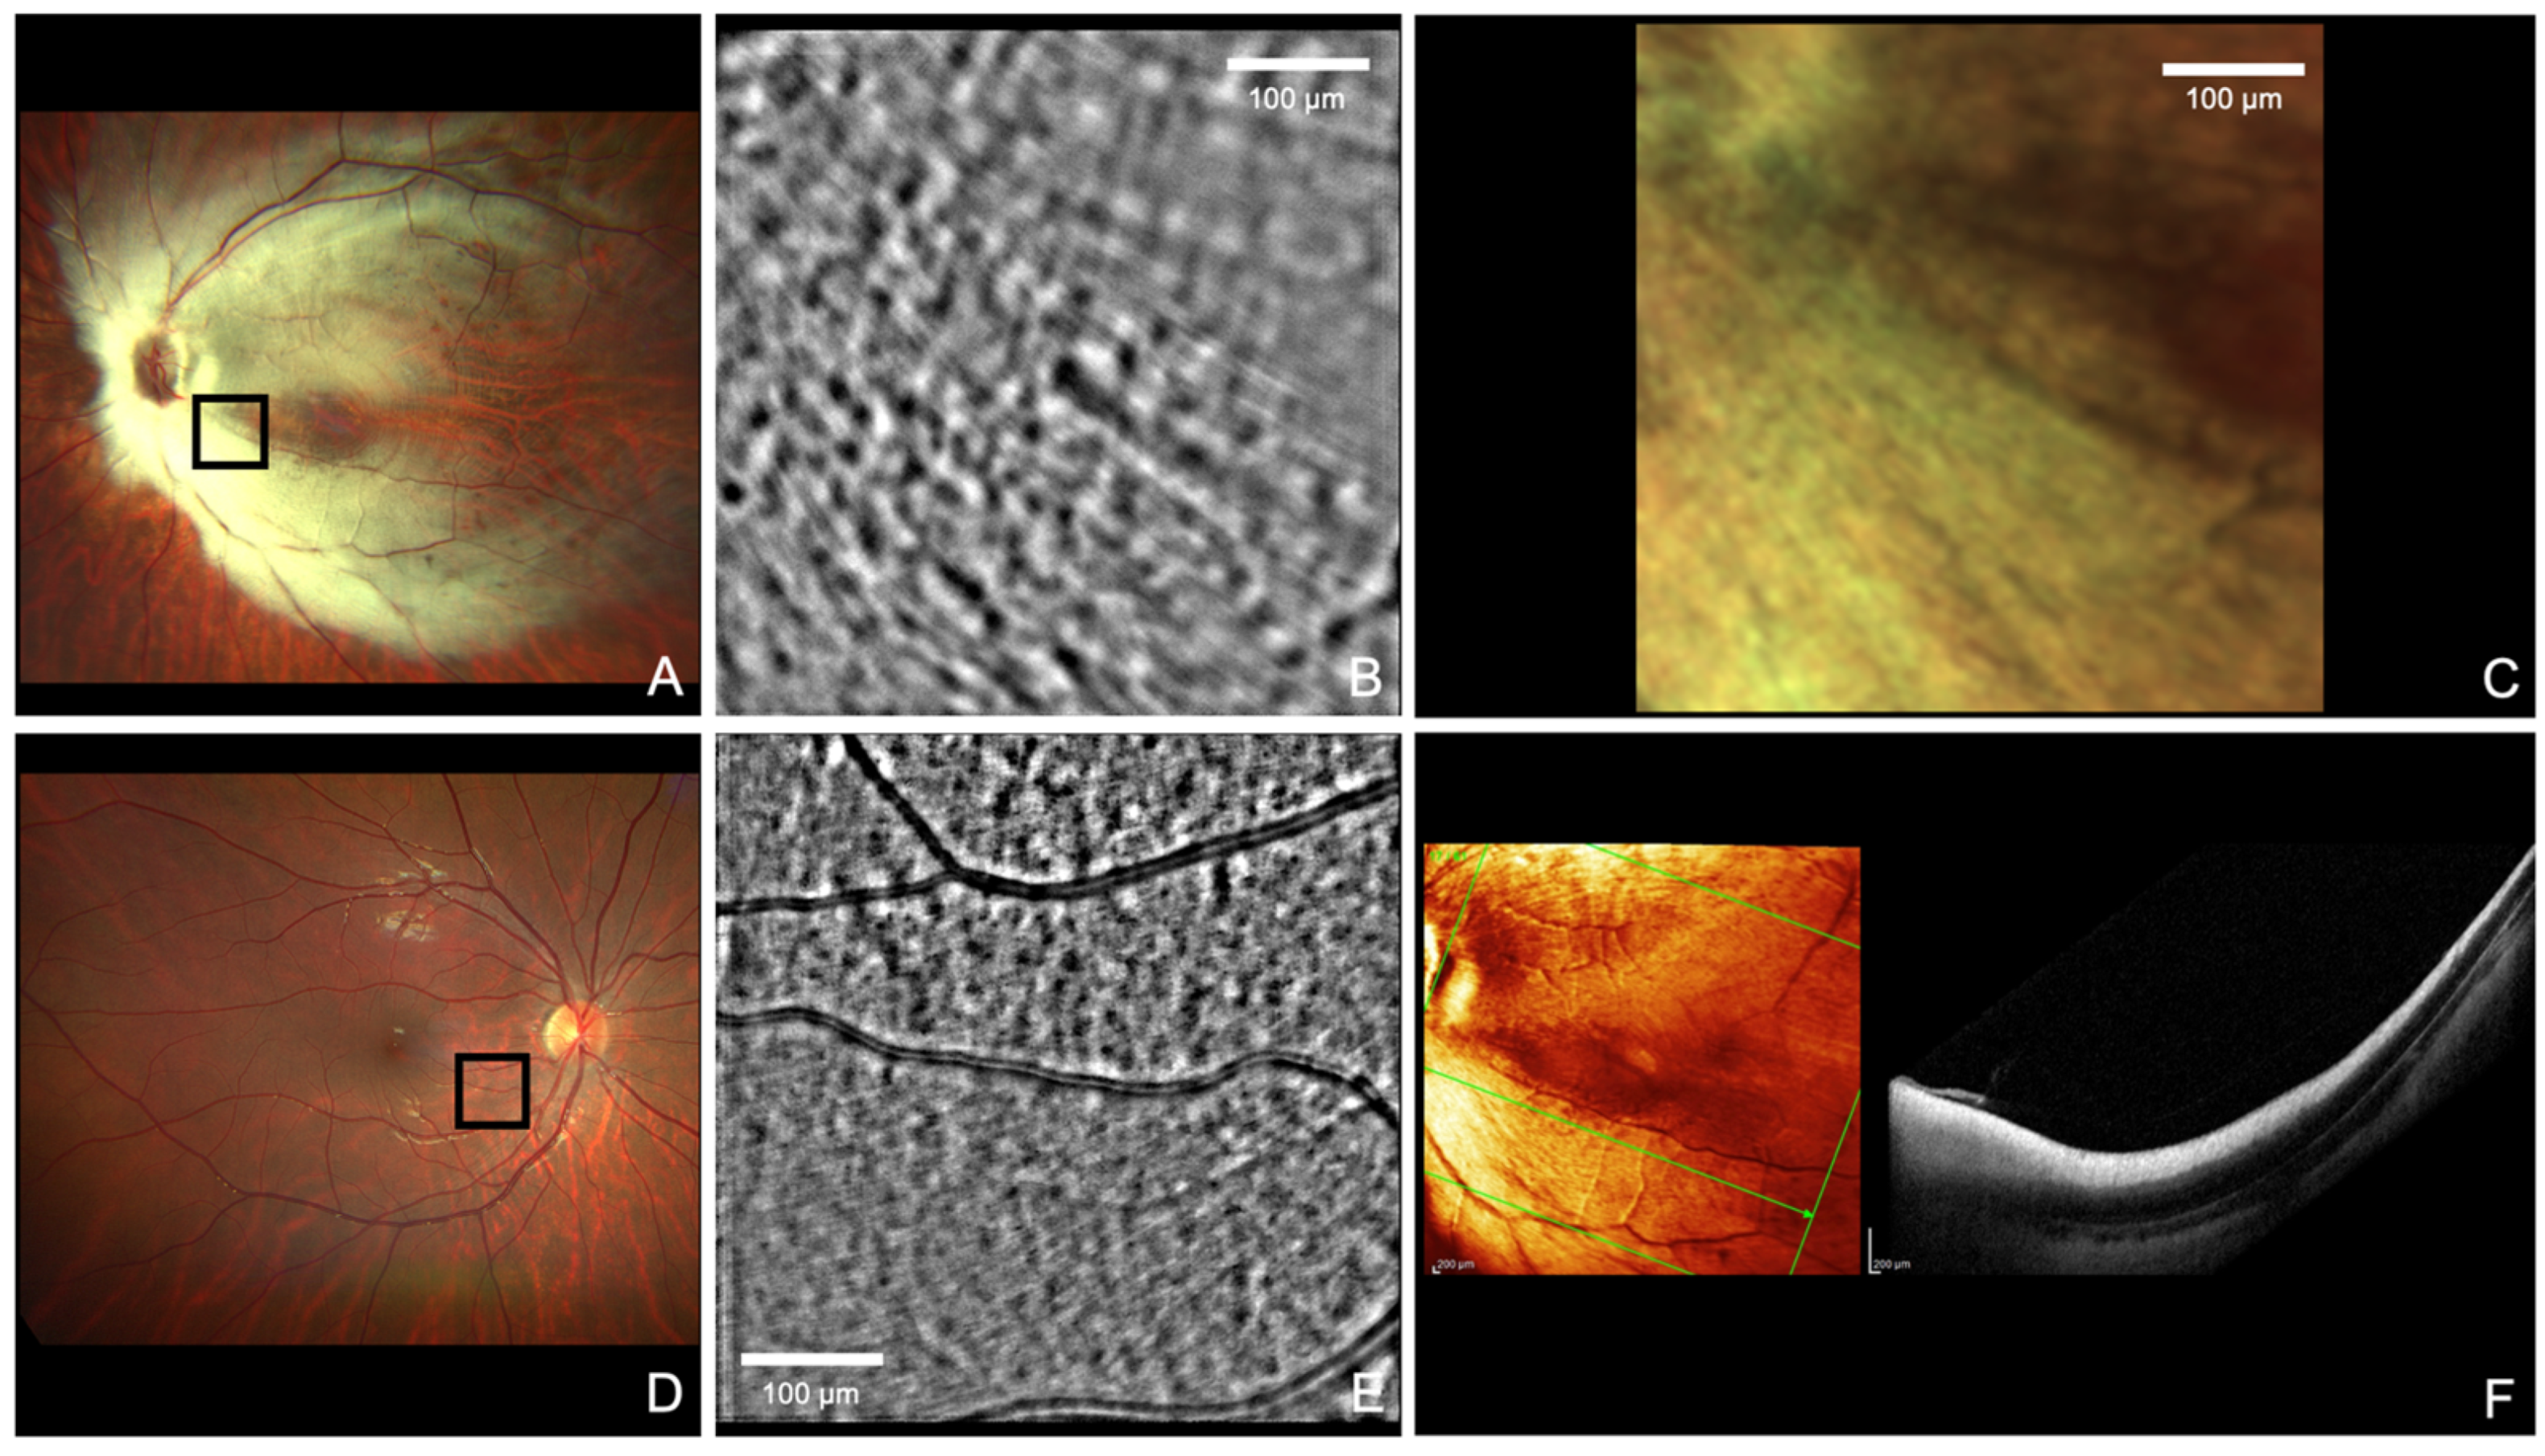

Non-Invasive High-Resolution Imaging of In Vivo Human Myelinated Axons

Lombardo, M.; Cesareo, M.; Falsini, B.; Cusumano, A. Non-Invasive High-Resolution Imaging of In Vivo Human Myelinated Axons. Diagnostics 2024, 14, 253. https://doi.org/10.3390/diagnostics14030253